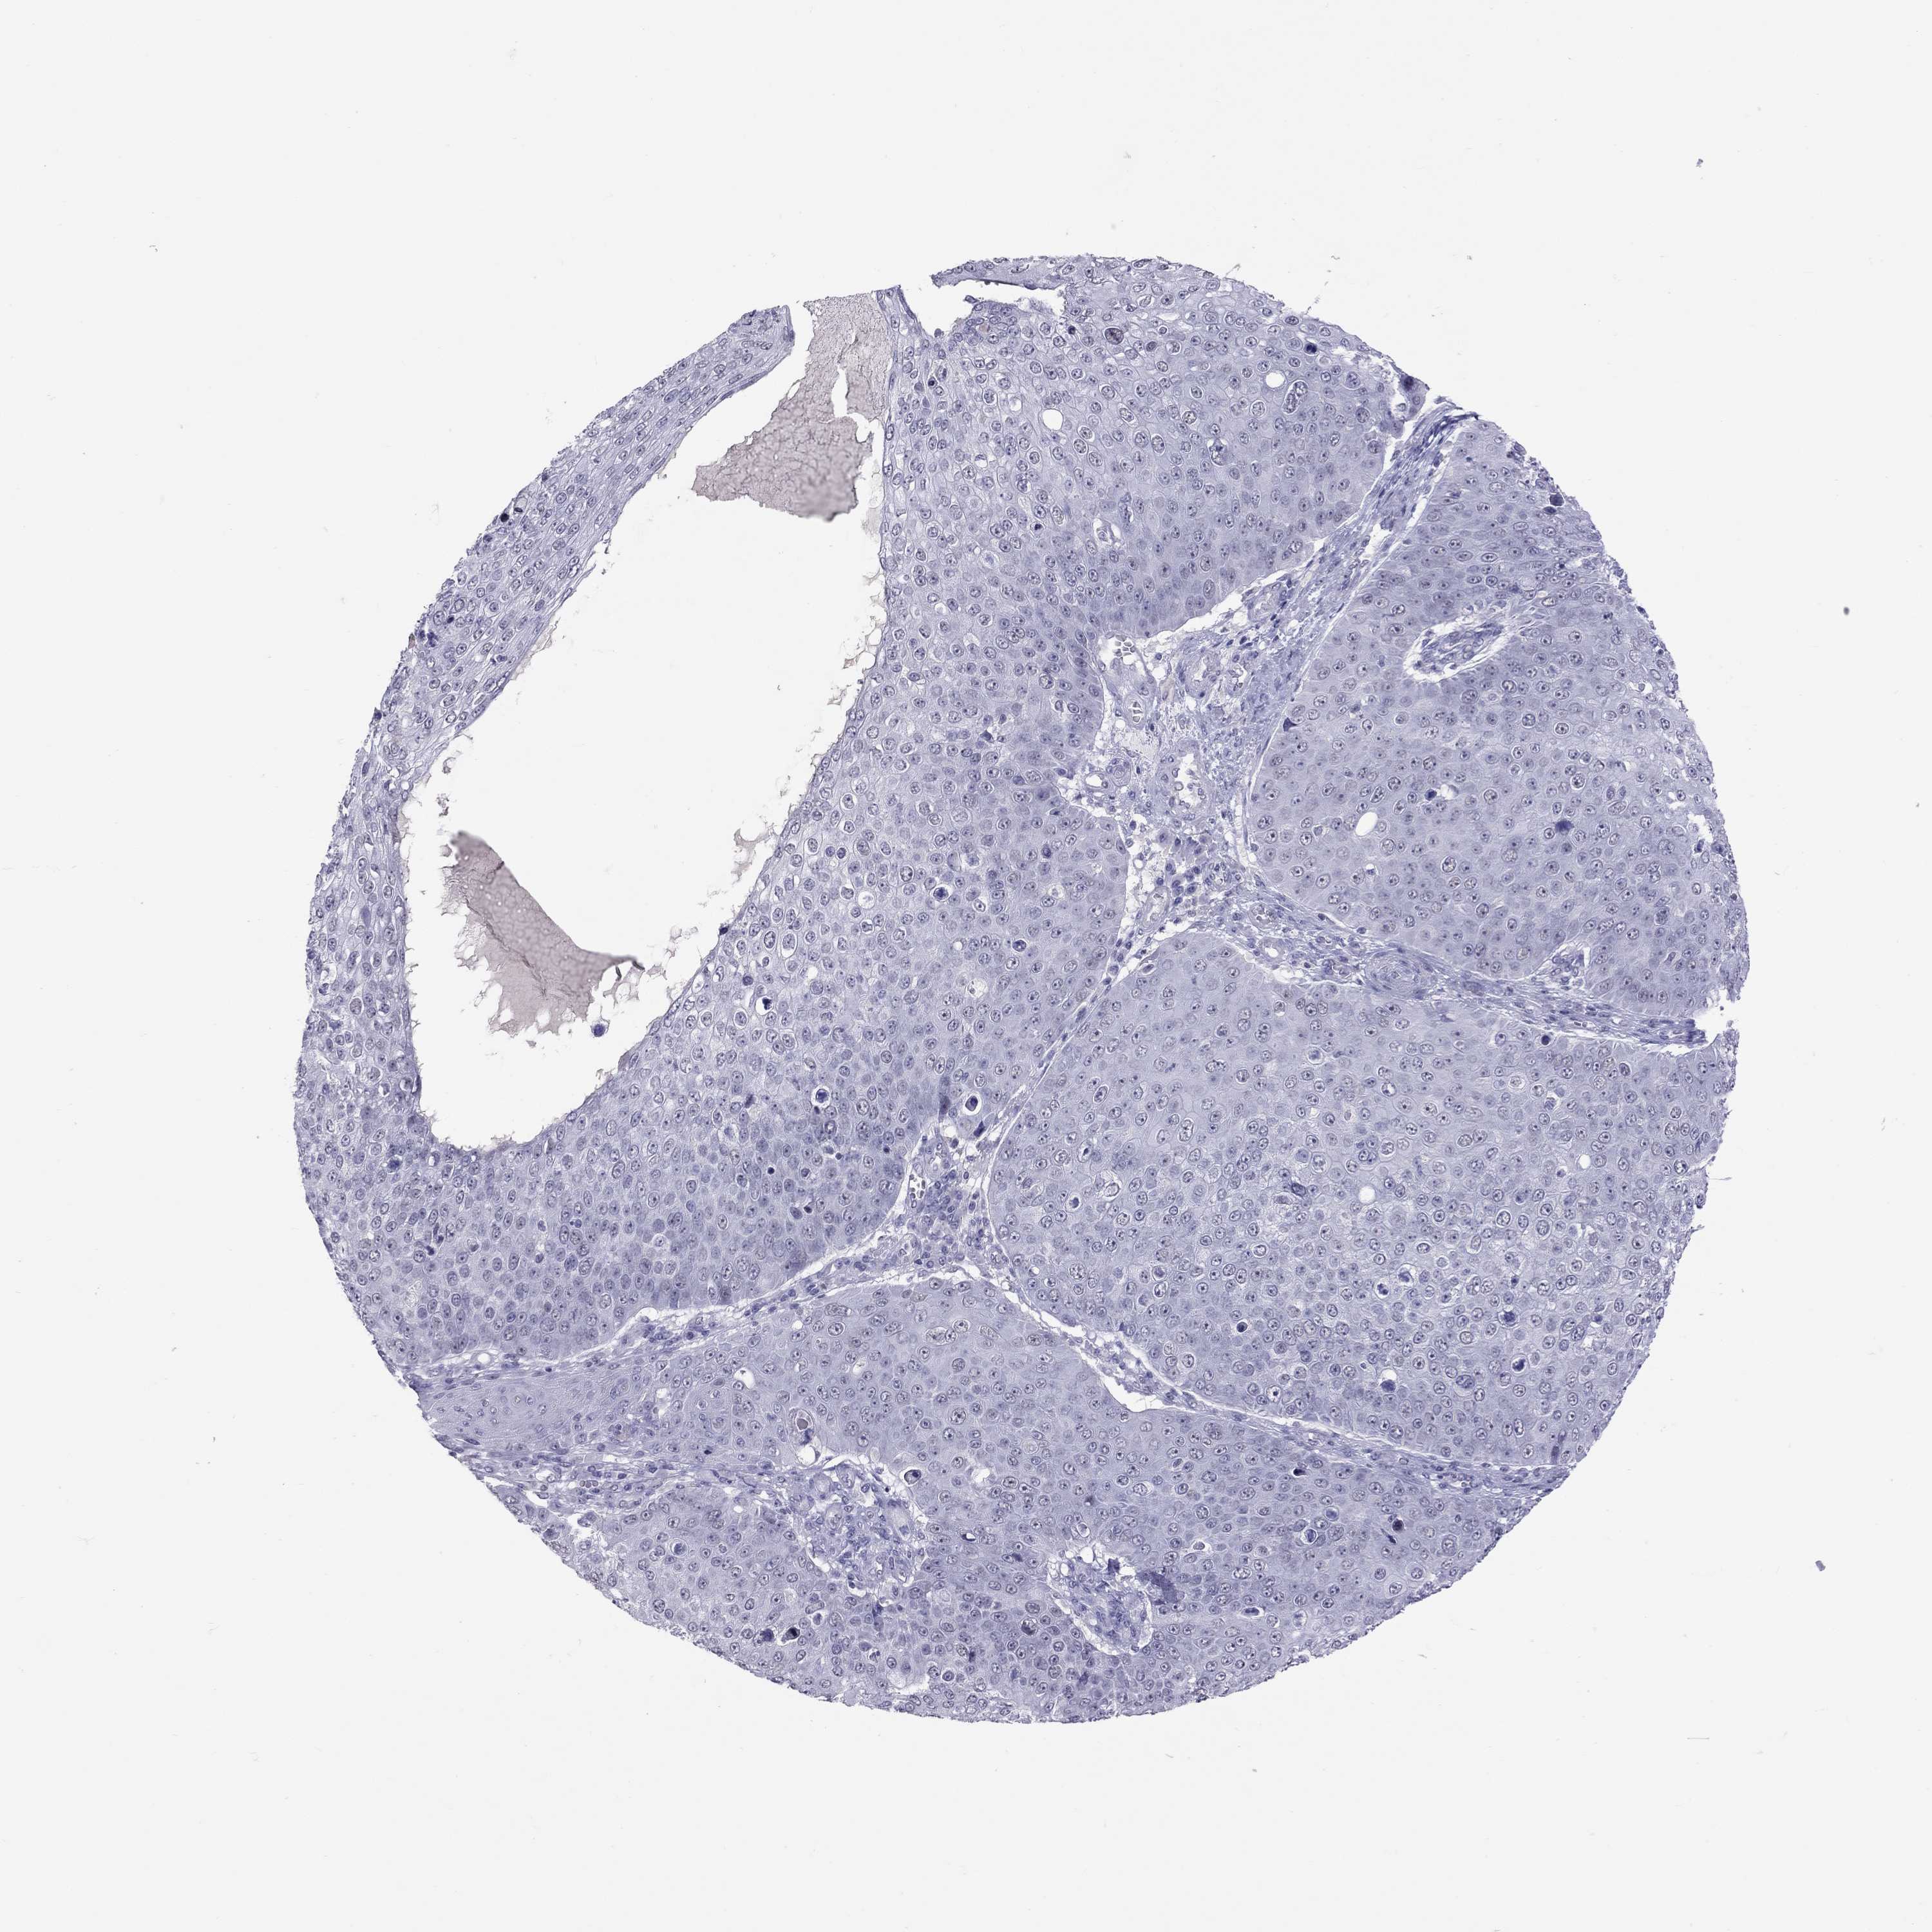

Basal cell and squamous cell cancer

SKIN CANCER - Protein expressioni

A mouse-over function shows sample information and annotation data. Click on an image to view it in a full screen mode. Samples can be filtered based on level of antibody staining by selecting one or several of the following categories: high, medium, low and not detected. The assay and annotation is described here.

Each image is clickable and will lead to virtual microscopy that enables deeper exploration of all samples and also displays staining intensity scores, fraction scores and subcellular localization as well as patient and tissue information for each sample.

Antibody HPA077658

Basal cell carcinoma

Squamous cell carcinoma, NOS